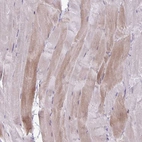

Immunohistochemical staining of human skeletal muscle shows moderate cytoplasmic positivity in myocytes.